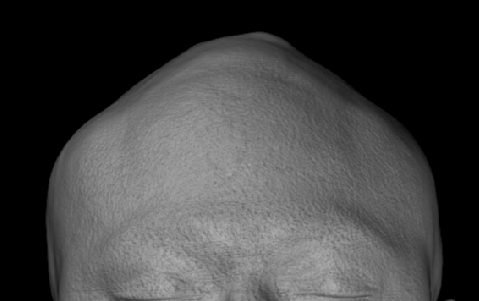

Severe narrowing skull deformity from prior sagittal craniosynostosis repair as an adult.

Complete replacement of entire skull by a custom implant with temporal fat injections.